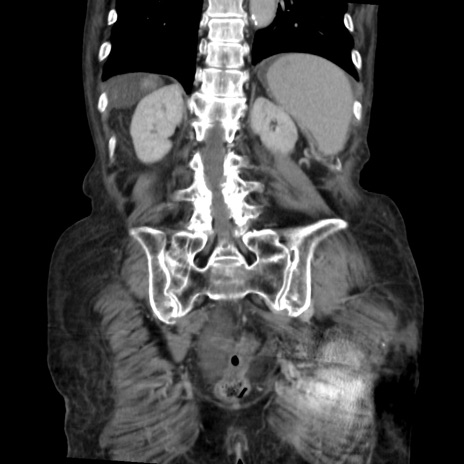

症例31(冠状断像)

【症例】80歳代 女性

【主訴】腹部膨満感

【現病歴】他院にて肝硬変にてフォロー中。1週間前から便秘、腹部膨満感、臍部腫瘤あり受診となる。

【既往歴】肝硬変

【身体所見】腹部膨隆あり、皮膚変化なし、疼痛なし。

【データ】WBC 4600、CRP 0.25